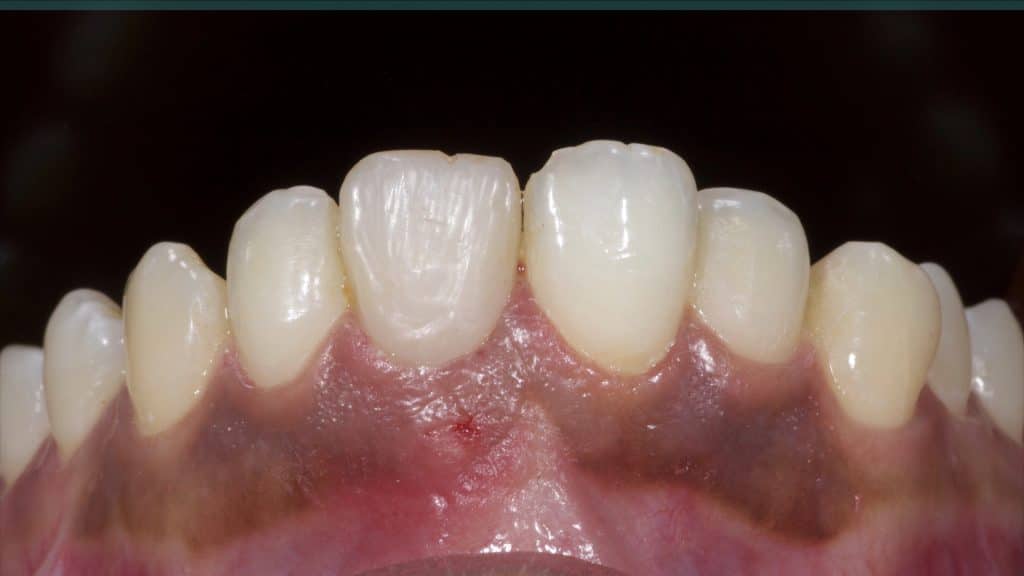

20 days post-op after suture removal